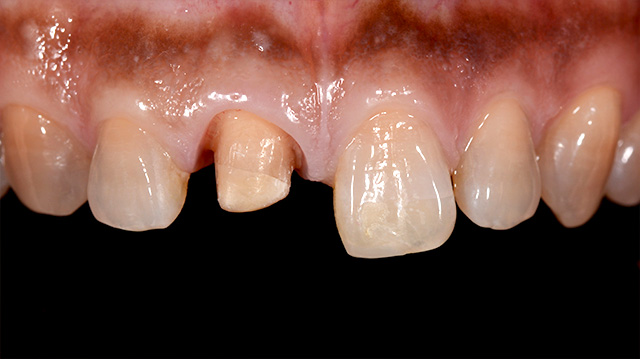

| 年代・性別 | 30代 男性 |

|---|---|

| 主訴 | 前歯の色が気になる |

| 治療期間 | 約1年 |

| 費用 |

仮歯 5,500円 × 2 ジルコニアクラウン 176,000円 × 3 インプラント 300,000円 インプラント仮歯 22,000円 サージカルガイド 70,000円 |

*キャンセルポリシーをご一読のうえご予約ください